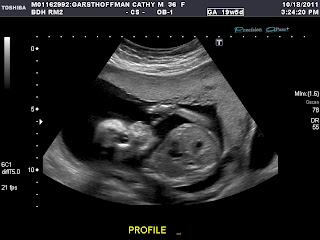

We found out today that we are having a little girl! Honestly, I was in complete shock for about 20 min. as I had always envisioned myself as being a mother to boys. Harrison did not take the news as well as we would have hoped and after a few tears were shed, he has become to enjoy the thoughts of being her protector and fending off the boys (he can use those muscles he has been working so hard to build)...he also likes the idea that he and his papa will be in the only "boys" in their club.